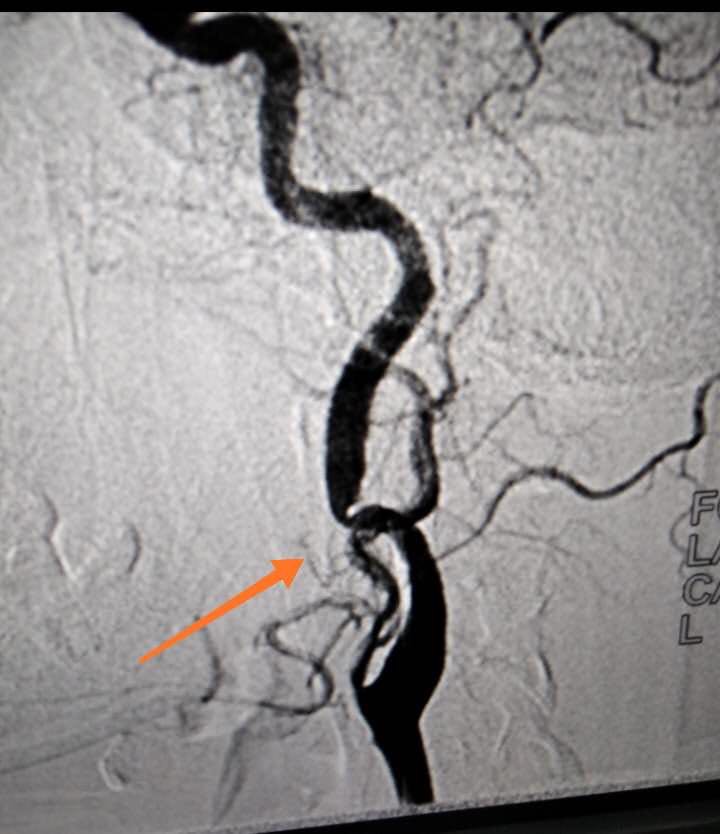

神經(jīng)內(nèi)科聯(lián)合介入中心首次成功開展全腦血管造影術(shù)

2020年7月20日對于我們菏澤醫(yī)專附屬醫(yī)院神經(jīng)內(nèi)科來說是一個不平凡的日子,在醫(yī)院領(lǐng)導(dǎo)、介入中心和兄弟科室的大力支持下,成功為一名患者實施了全腦血管造影術(shù),標志著我院在神經(jīng)系統(tǒng)疾病診治方面取得了突破性進展。

患者青年女性,發(fā)作性頭暈多年,輾轉(zhuǎn)各地醫(yī)院進行診治,均未明確具體原因。經(jīng)我院給予全腦血管造影術(shù),發(fā)現(xiàn)病變血管,明確病因,為以后的診治確立了正確的方向。首次開展此項檢查,對我們醫(yī)護人員是一個重大考驗,從術(shù)前準備到成功完成檢查再到術(shù)后護理,我們醫(yī)護人員能夠熟練掌握流程,嚴格遵守各項操作規(guī)范,使患者快速有效完成檢查?;颊弑硎緦χ委熜Ч軡M意。

全腦血管造影術(shù)是在數(shù)字減影血管造影(DSA)系統(tǒng)的支持下,采用血管內(nèi)導(dǎo)管操作技術(shù),通過選擇性造影、栓塞、擴張成形、機械清除、藥物遞送等具體方法,對累及人體神經(jīng)血管系統(tǒng)的病變進行診斷和治療。它是一種微創(chuàng)臨床技術(shù),為許多腦與脊髓血管疾病開辟了新的思路和治療途徑。既可以獨立解決許多腦血管疾病,又可以和傳統(tǒng)的開放手術(shù)、放射治療等巧妙結(jié)合,使原來無法或難以治療的疾病得到滿意療效。它不但能提供病變的確切部位,而且可以清楚地了解病變的范圍、嚴重程度、與周圍血管的關(guān)系等細節(jié),對確立治療方案指導(dǎo)進一步治療有重要意義。

全腦血管造影術(shù)主要是治療腦與脊髓血管病,在腦腫瘤、脊柱腫瘤等疾病的治療也有涉及。治療方向包括1.缺血性腦血管病:腦動脈狹窄,急性或慢性腦動脈閉塞,顱內(nèi)靜脈竇血栓等。2.出血性腦血管?。耗X動脈瘤,腦動靜脈畸形、動靜脈瘺、脊髓-脊柱血管畸形等。3.腦-脊髓脊柱腫瘤類:富血運腫瘤術(shù)前造影評估與栓塞,惡性腦腫瘤動脈內(nèi)超選擇性化療等

菏澤醫(yī)專附屬醫(yī)院成功開展全腦血管造影術(shù)標志著我院神經(jīng)內(nèi)科在診斷技術(shù)方面又邁上了一個新的臺階,進一步提高了我院腦血管病的醫(yī)療救治水平,同時為下一步腦血管內(nèi)介入治療墊定了基礎(chǔ),為廣大急性腦血管病患者提供了更加便捷高效的就醫(yī)環(huán)境!